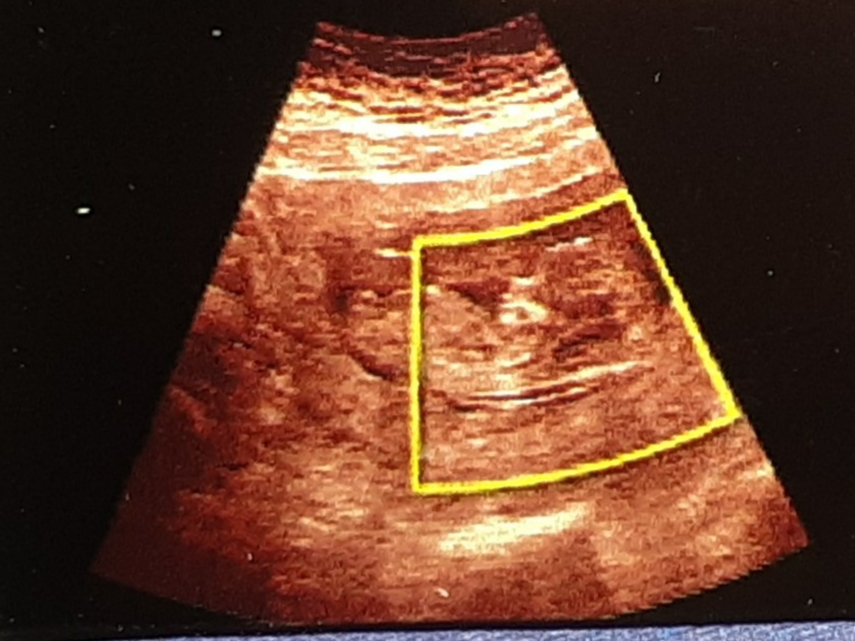

قا۳دک مدیر استارتر عضویت: 1397/07/29 تعداد پست: 3551 سلام گلم میشه محبت کنی جنسیت نی نی منو حدس بزنی؟ شبیه دختره

۲۷۷۷۴ عضویت: 1398/03/19 تعداد پست: 2303 شبیه دختره سلام گلم خوبی میشه لطف کنی سونو انتی بچه منم نگاه کنی ببینی جنسیت چیه؟؟

seeeeliiin عضویت: 1400/11/10 تعداد پست: 109 سلام عزیزم عکست خیلی ناواضحه ولی بخاطر تحدب پشتش حس میکنم پسره انشاالله صحیح و سالم باشه 💗😘 برای منم میشه بگی ????